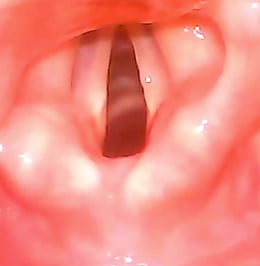

"I am pleased to report that the OneScope is performing brilliantly and is considered a very valuable tool in the midst of the COVID pandemic. As you may already be aware, much publicity has been released regarding the risks of intubation of a COVID positive patient. Much of the risk can be mitigated by the use of portable video laryngoscopes. I have instituted the OneScope as the primary tool for intubation of these patients, primarily due to it’s portability, ease of use, ease/speed of decontamination and ability to review the intubation via video and screen shot"